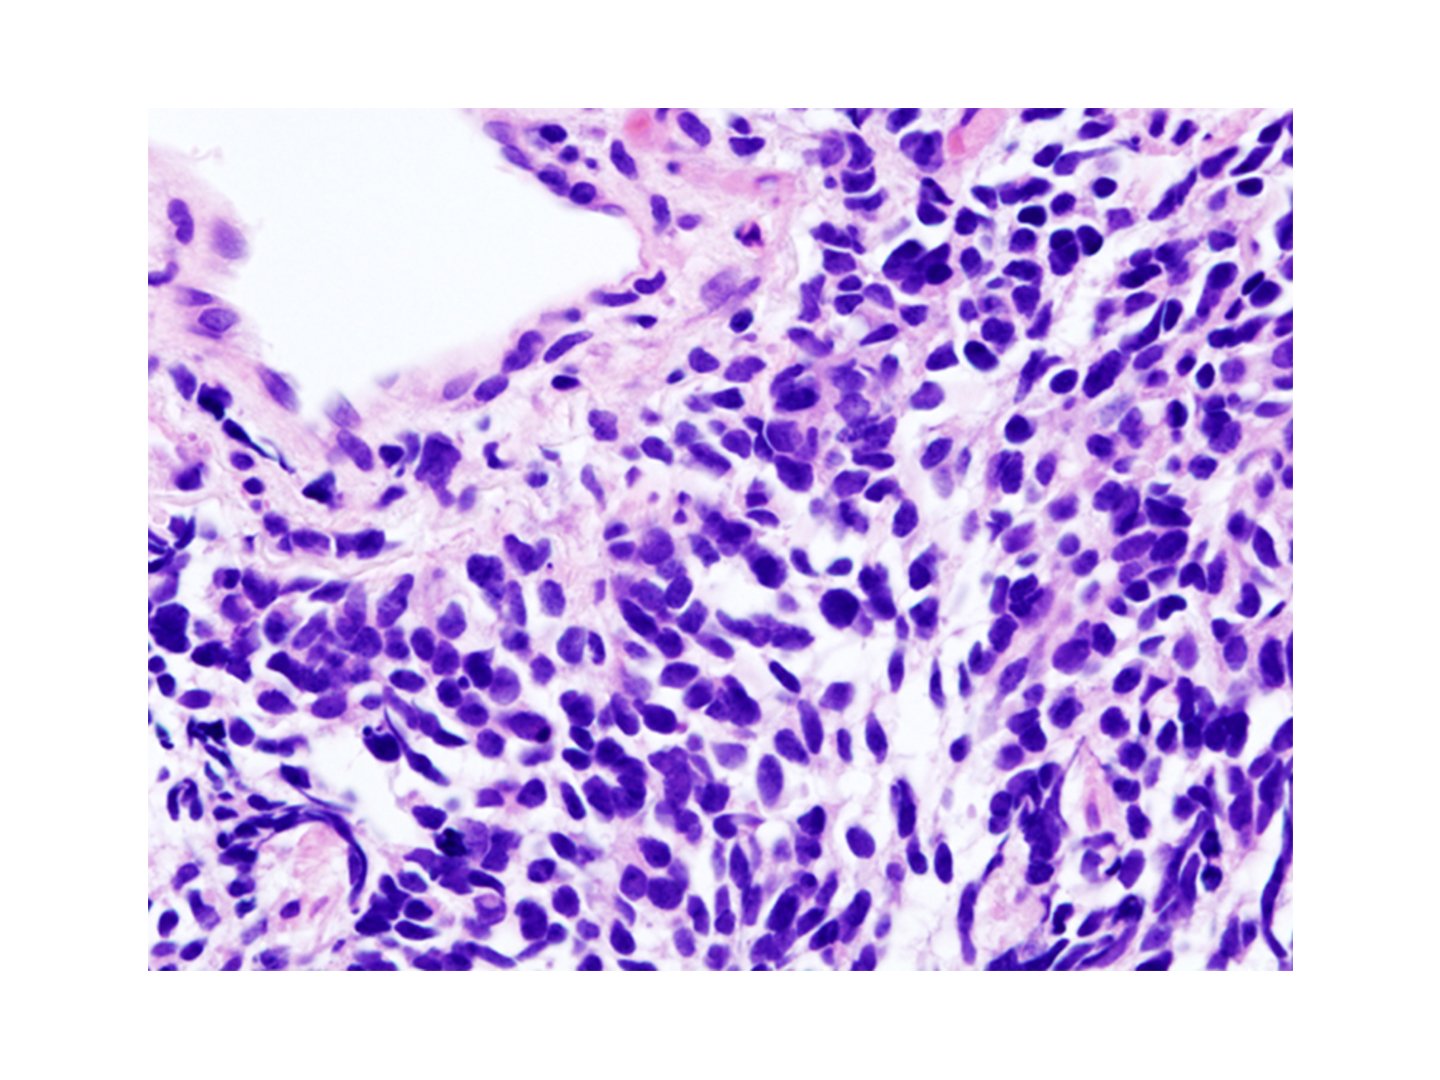

Kleinzelliges Lungenkazinom

Kleinzelliges Lungenkarzinom

Engl. small cell lung carcinoma (SCLC)

Schnelles Wachstum

SCLC wächst sehr schnell und metastasiert daher sehr früh.